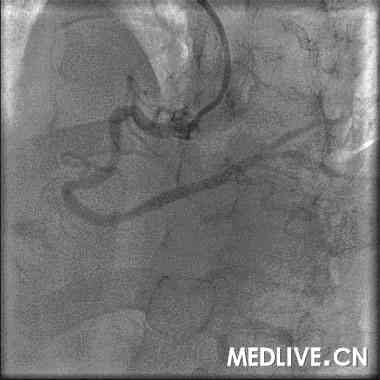

1.造影结果:右冠三叉前严重狭窄(图1)

图1 造影结果